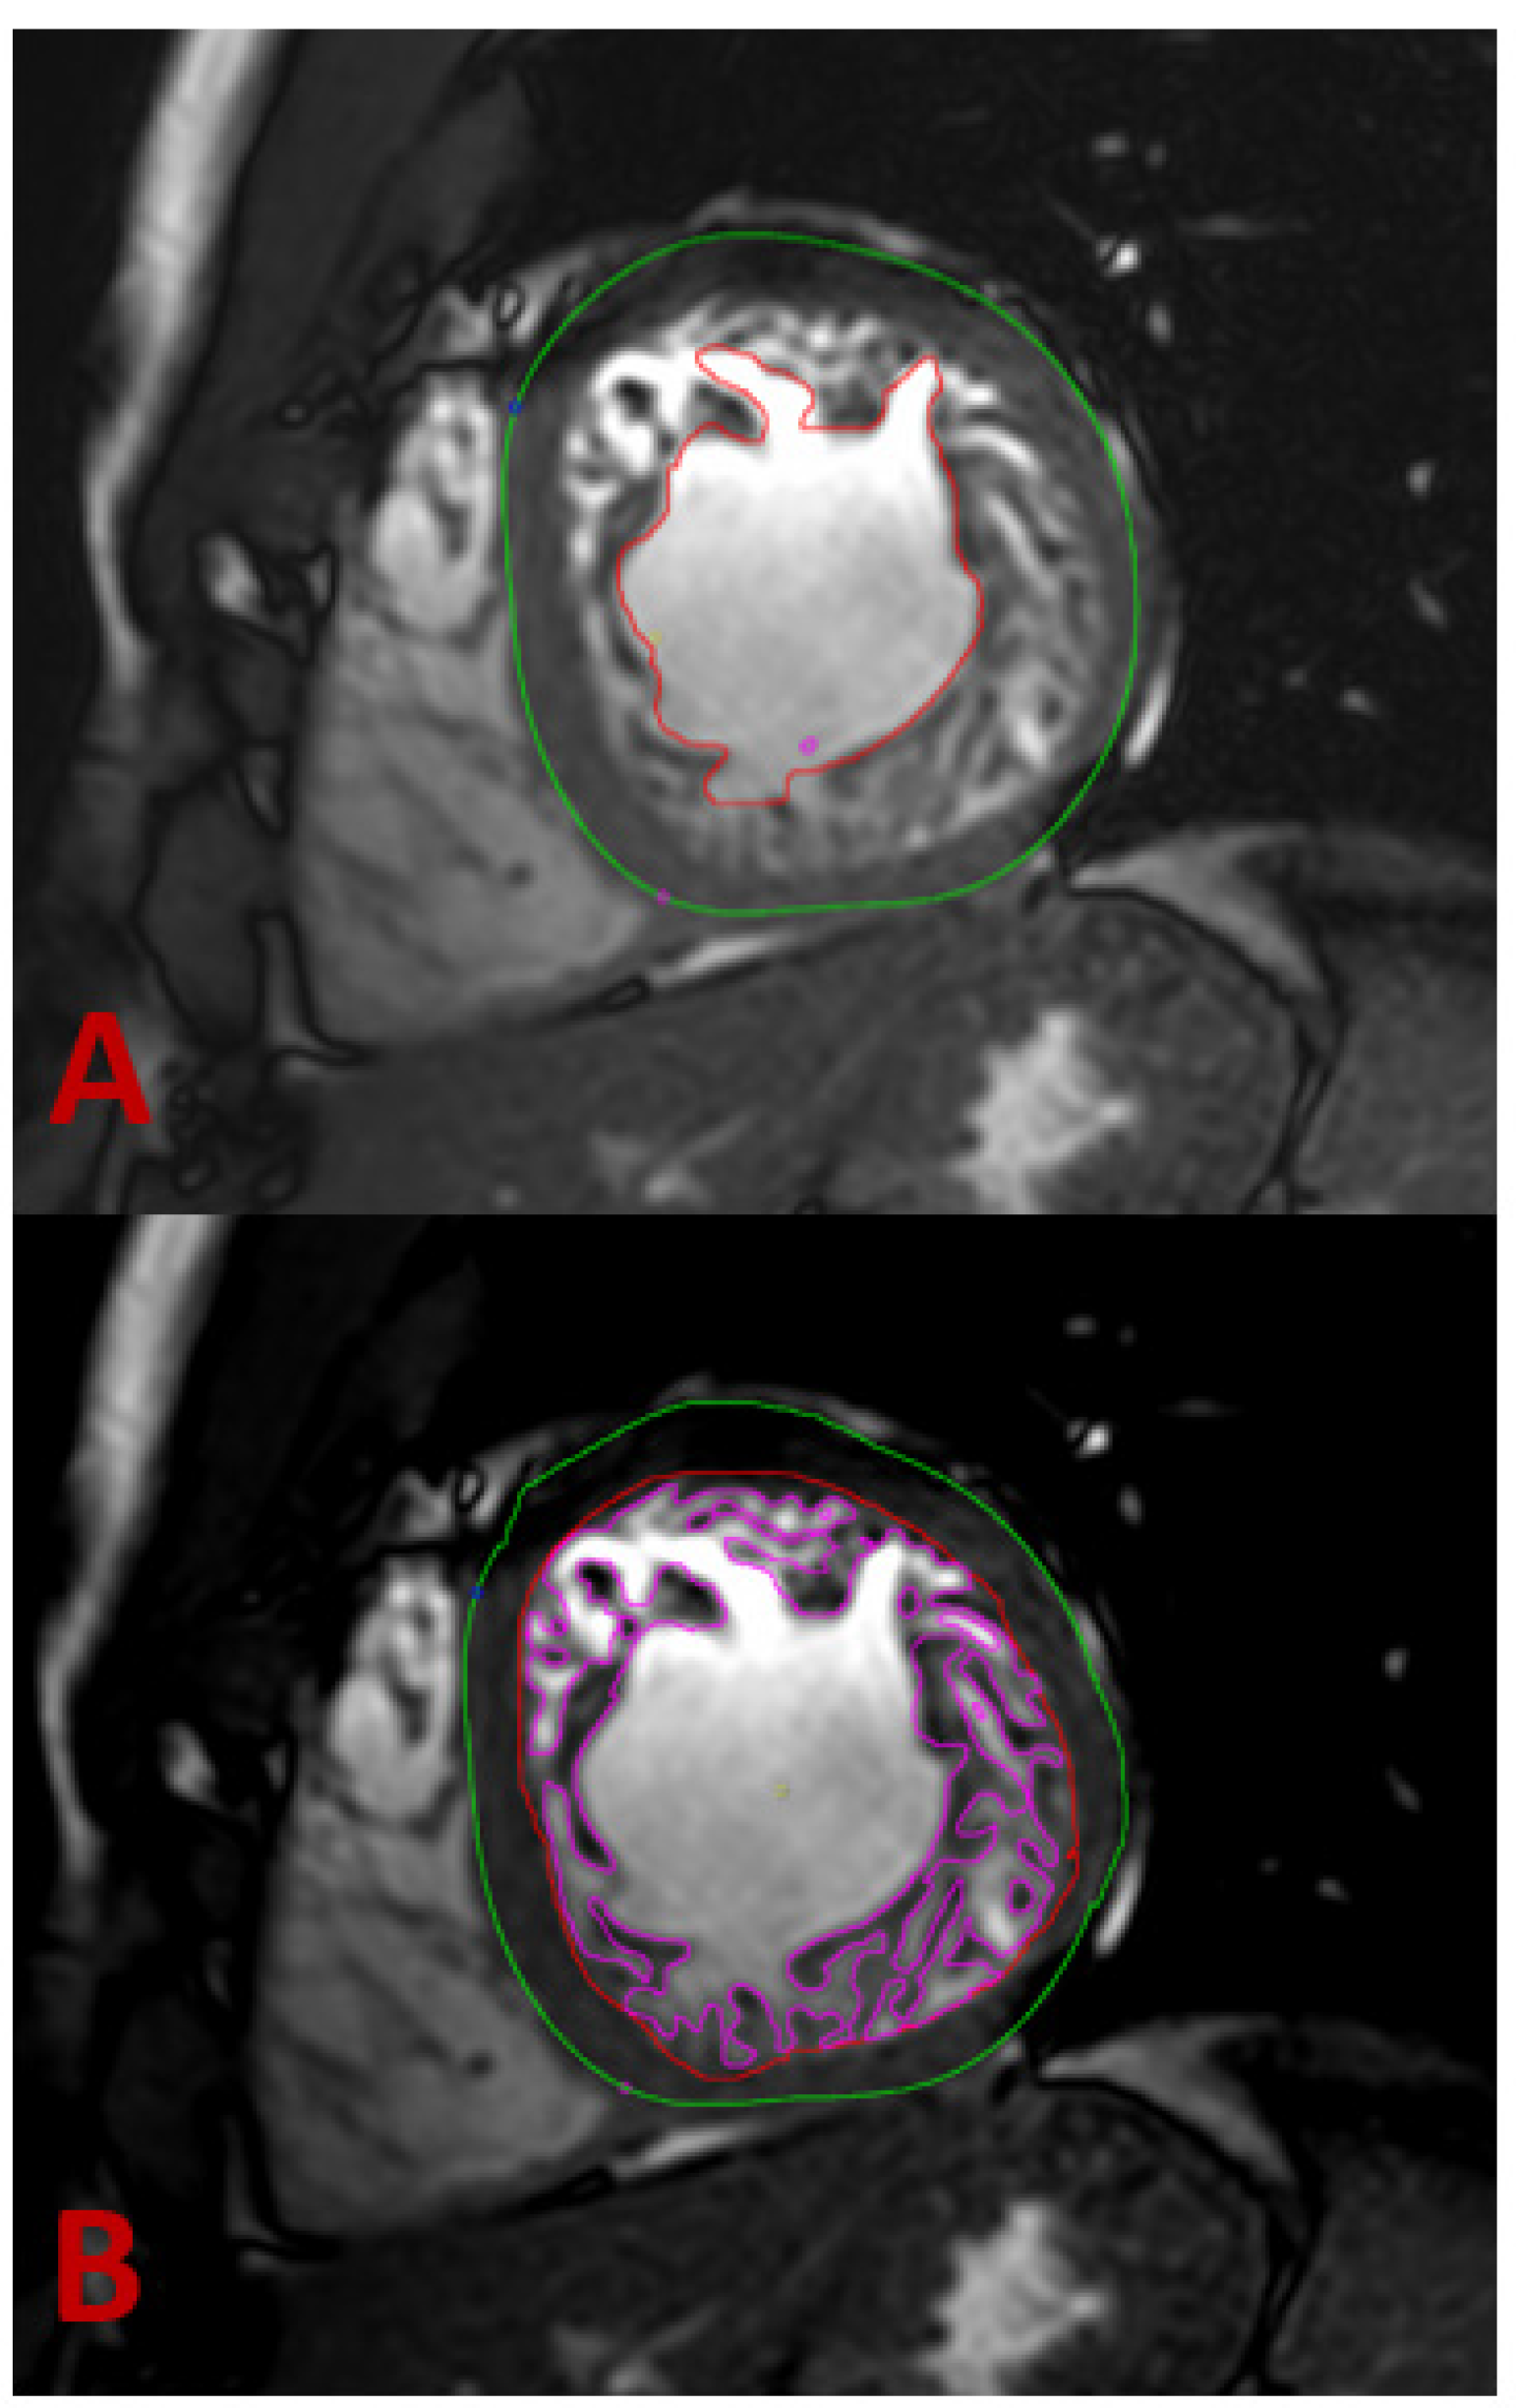

- Petersen, S.E.; Selvanayagam, J.B.; Wiesmann, F.; Robson, M.D.; Francis, J.M.; Anderson, R.H.; Watkins, H.; Neubauer, S. Left ventricular non-compaction: Insights from cardiovascular magnetic resonance imaging. J. Am. Coll. Cardiol. 2005, 46, 101–105. [Google Scholar] [CrossRef]

- Stacey, R.B.; Andersen, M.M.; St Clair, M.; Hundley, W.G.; Thohan, V. Comparison of systolic and diastolic criteria for isolated LV noncompaction in CMR. JACC Cardiovasc. Imaging 2013, 6, 931–940. [Google Scholar] [CrossRef]

- Jacquier, A.; Thuny, F.; Jop, B.; Giorgi, R.; Cohen, F.; Gaubert, J.Y.; Vidal, V.; Bartoli, J.M.; Habib, G.; Moulin, G. Measurement of trabeculated left ventricular mass using cardiac magnetic resonance imaging in the diagnosis of left ventricular non-compaction. Eur. Heart J. 2010, 31, 1098–1104. [Google Scholar] [CrossRef]

- Choi, Y.; Kim, S.M.; Lee, S.C.; Chang, S.A.; Jang, S.Y.; Choe, Y.H. Quantification of left ventricular trabeculae using cardiovascular magnetic resonance for the diagnosis of left ventricular non-compaction: Evaluation of trabecular volume and refined semi-quantitative criteria. J. Cardiovasc. Magn. Reson. 2016, 18, 24. [Google Scholar] [CrossRef] [PubMed]

- Captur, G.; Muthurangu, V.; Cook, C.; Flett, A.S.; Wilson, R.; Barison, A.; Sado, D.M.; Anderson, S.; McKenna, W.J.; Mohun, T.J.; et al. Quantification of left ventricular trabeculae using fractal analysis. J. Cardiovasc. Magn. Reson. 2013, 15, 36. [Google Scholar] [CrossRef] [PubMed]